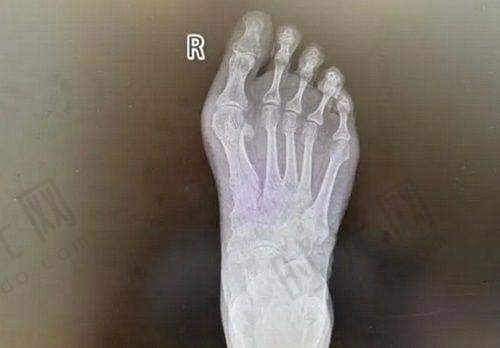

骨愈合期(术后3-8周):长骨头的关键期。术后4周左右,X光片可见骨痂开始形成,此时可在医生指导下进行被动活动(如他人辅助屈伸),但需避免负重。临床统计显示,儿童患者骨愈合速度比成人快30%-40%,而糖尿病患者或吸烟者可能延迟2-3周。这个阶段更忌讳过早用力,曾有患者因术后5周提重物导致钢板断裂,不得不二次手术。

并非所有骨折手指再造患者都需要二次手术,但当出现以下情况时,医生会建议进行二期修复:①骨折不愈合或延迟愈合(术后3个月X光仍可见清晰骨折线);②内固定物松动、断裂或刺激皮肤;③肌腱粘连导致关节活动度<正常范围的50%;④神经瘤形成引起顽固性疼痛。

重点提示:二次手术的必要性需通过临床评估(如CT三维重建、关节活动度测量)确定,患者切勿因急于修复而要求提前手术。2024年某三等甲医院统计显示,盲目提前二次手术的患者中,30%出现术后感染或骨折移位。